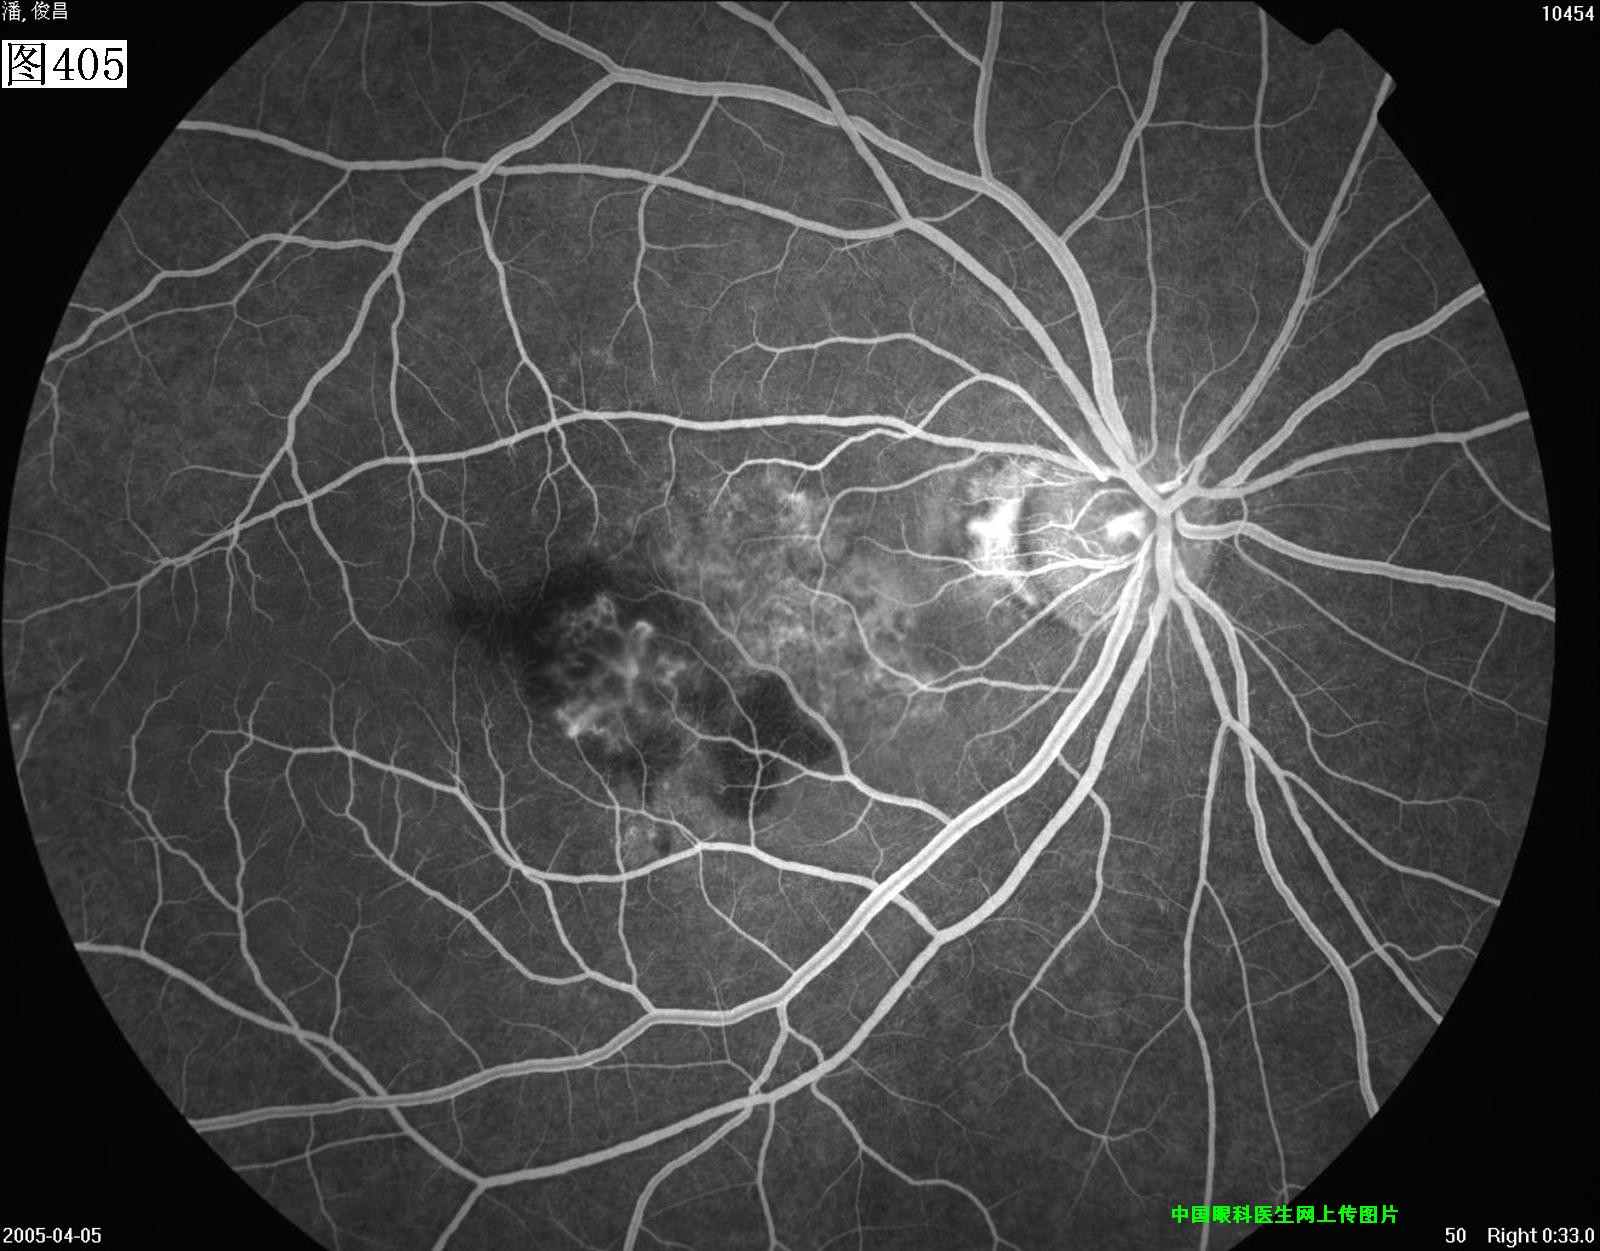

405 406 407 408